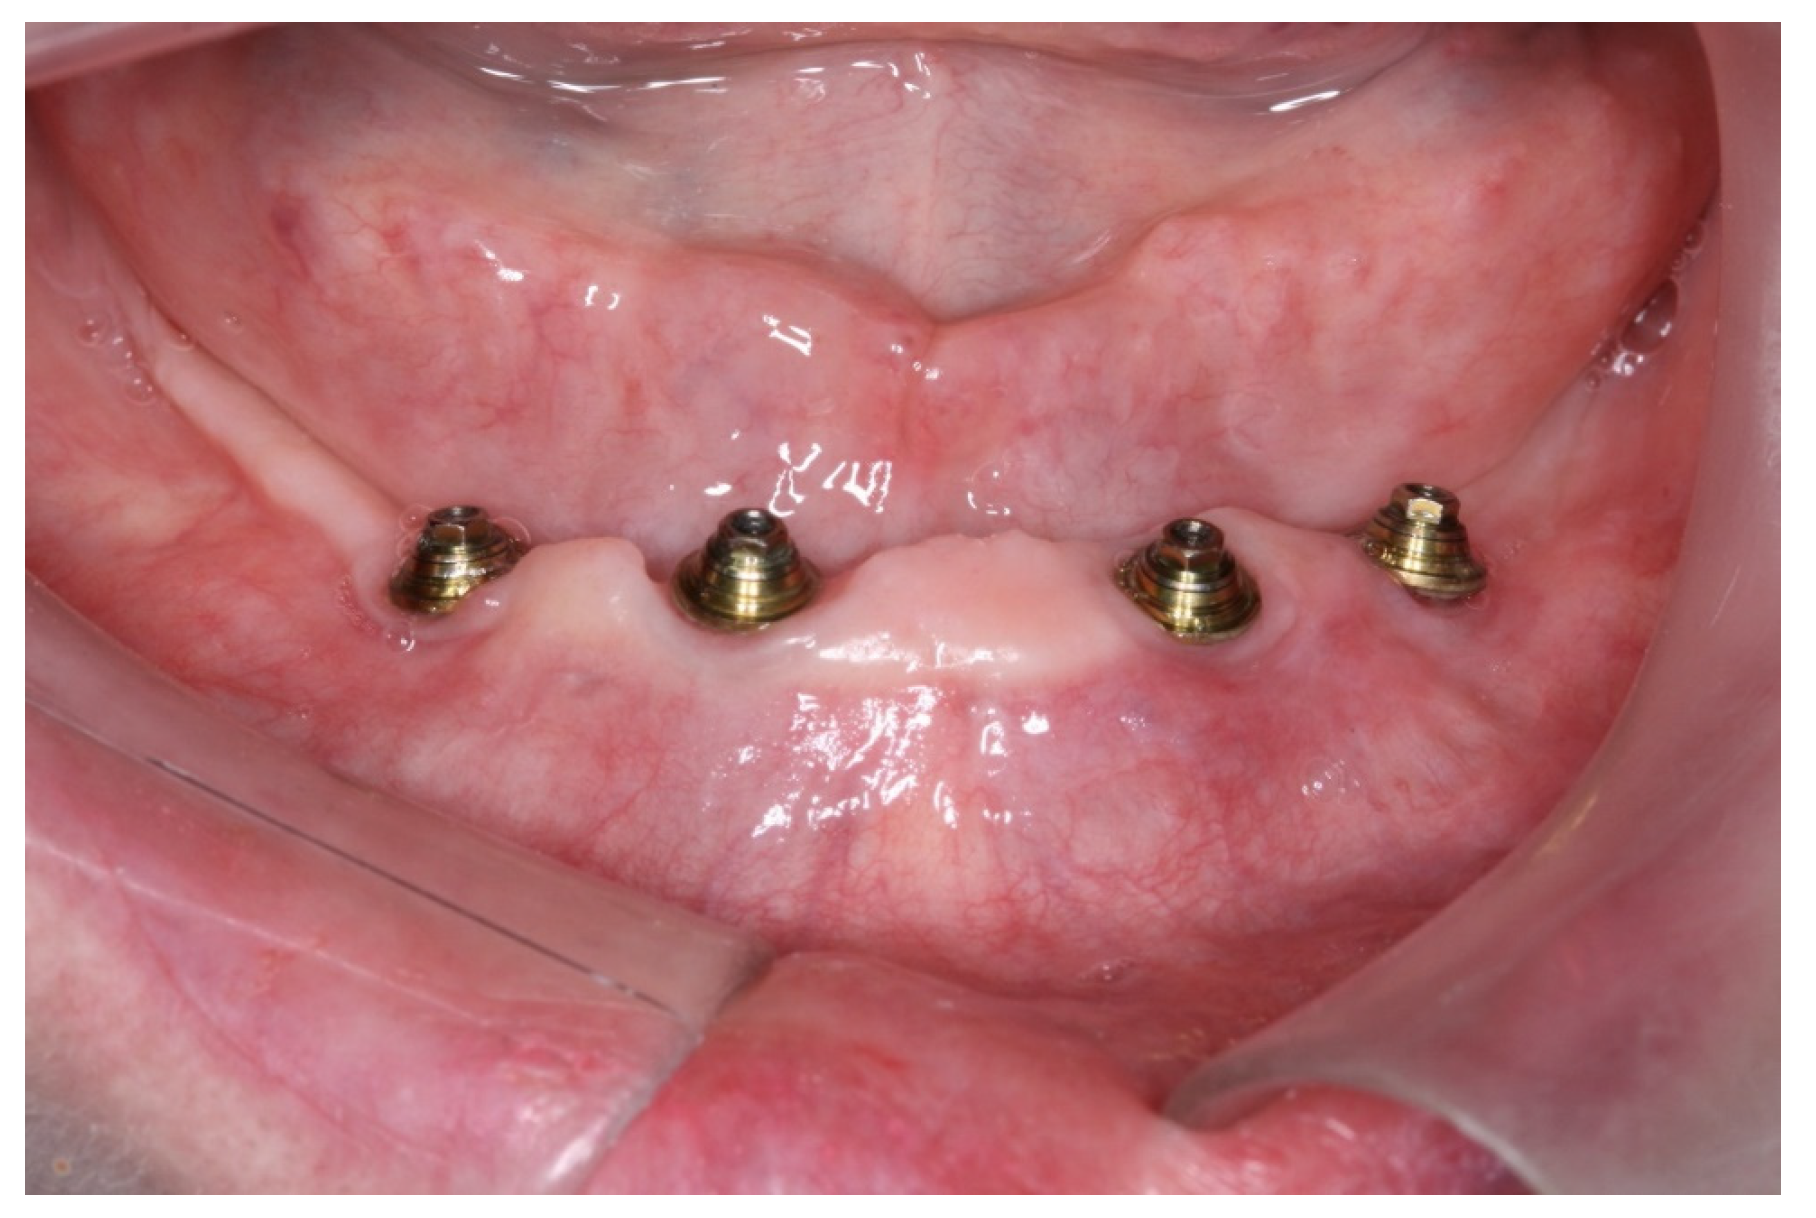

2. Case Report